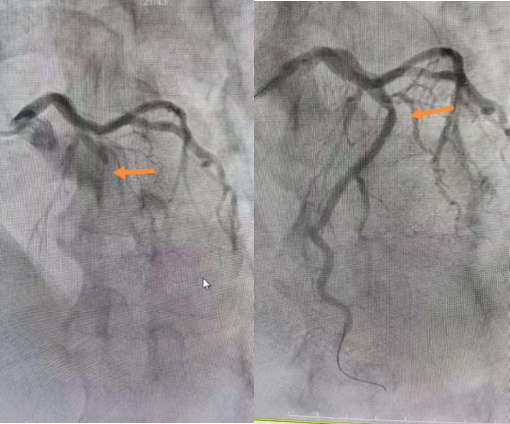

一切准备就绪,手术开始。冠脉造影发现患者前降支近段完全闭塞,立即予以置入两枚支架,迅速开通了闭塞的冠脉。导丝通过时间仅用17分钟,手术完成,过程顺利。术后,患者感觉胸痛明显好转,医护人员护送患者至CCU继续进一步治疗。